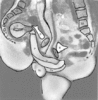

Eindrucksvolle und hochseriöse Studie, in der die genauen anatomischen Verhältnisse während des Koitus mittels Magnetresonanztomographie dargestellt wurden.

Der Text ist natürlich im klassischen Jargon einer medizinisch-wissenschaftlichen Studie gehalten, aber trotzdem stellenweise recht witzig, wenn Methoden und Kollektiv-recruitment beschrieben werden.

Die Erklärung zu diesem Schema erscheint, wenn man auf das Bild in der Studie klickt. Aber zum besseren Verständnis: links=Frau, rechts=Mann